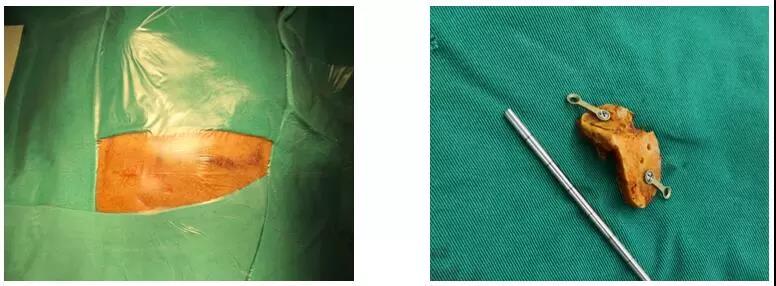

术中切口及骨瓣